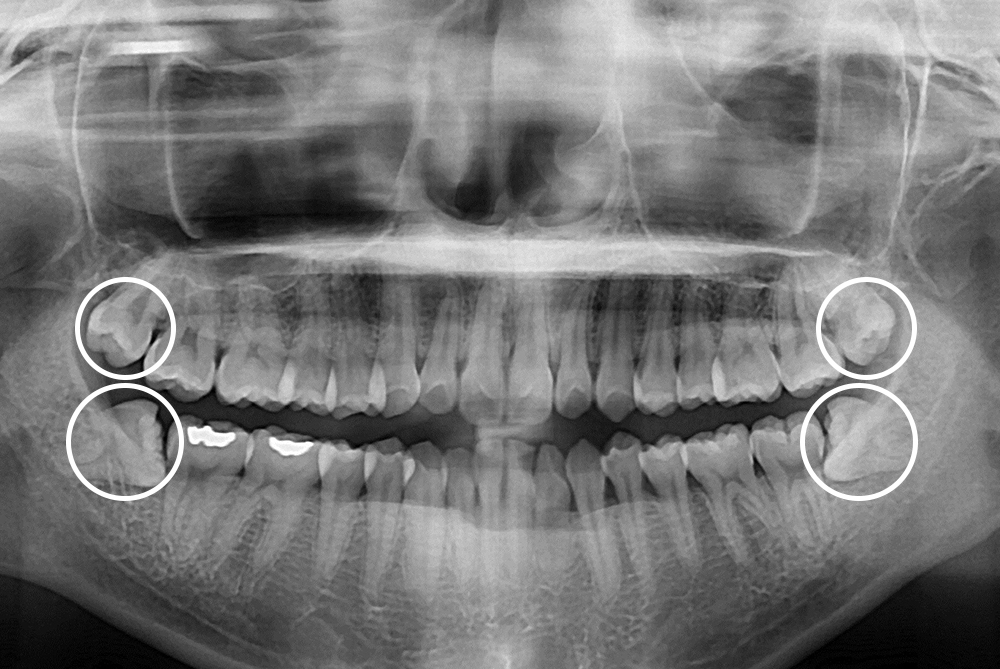

[사랑니] 매복 사랑니 발치

치료후 : 2019-02-07